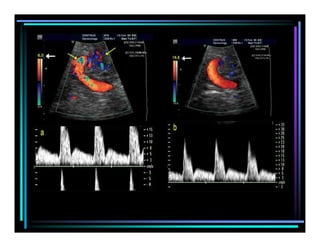

3) Color Doppler

1) Continuous wavedoppler • Without B MODE imaging 2) Pulsed wave doppler • Pulsed Doppler ultrasound is a technique for measuring the velocity of blood in a small sample volume • Used in general & obstetric ultrasound & also used to provide data for doppler sonograms & colour flow images. Disadvantage – “Aliasing” 3) Color Doppler